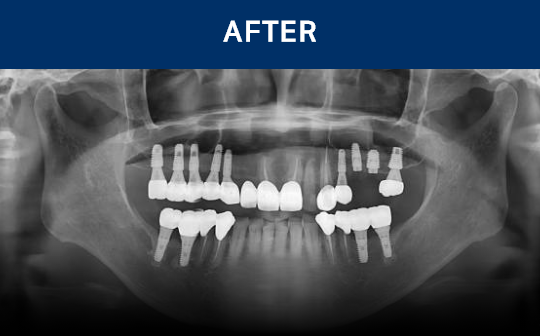

通过CT, 扫描等数字设

备拍摄后,

进行精密分析

考虑骨骼状态与神经位置,

制定种植位置与手术计划